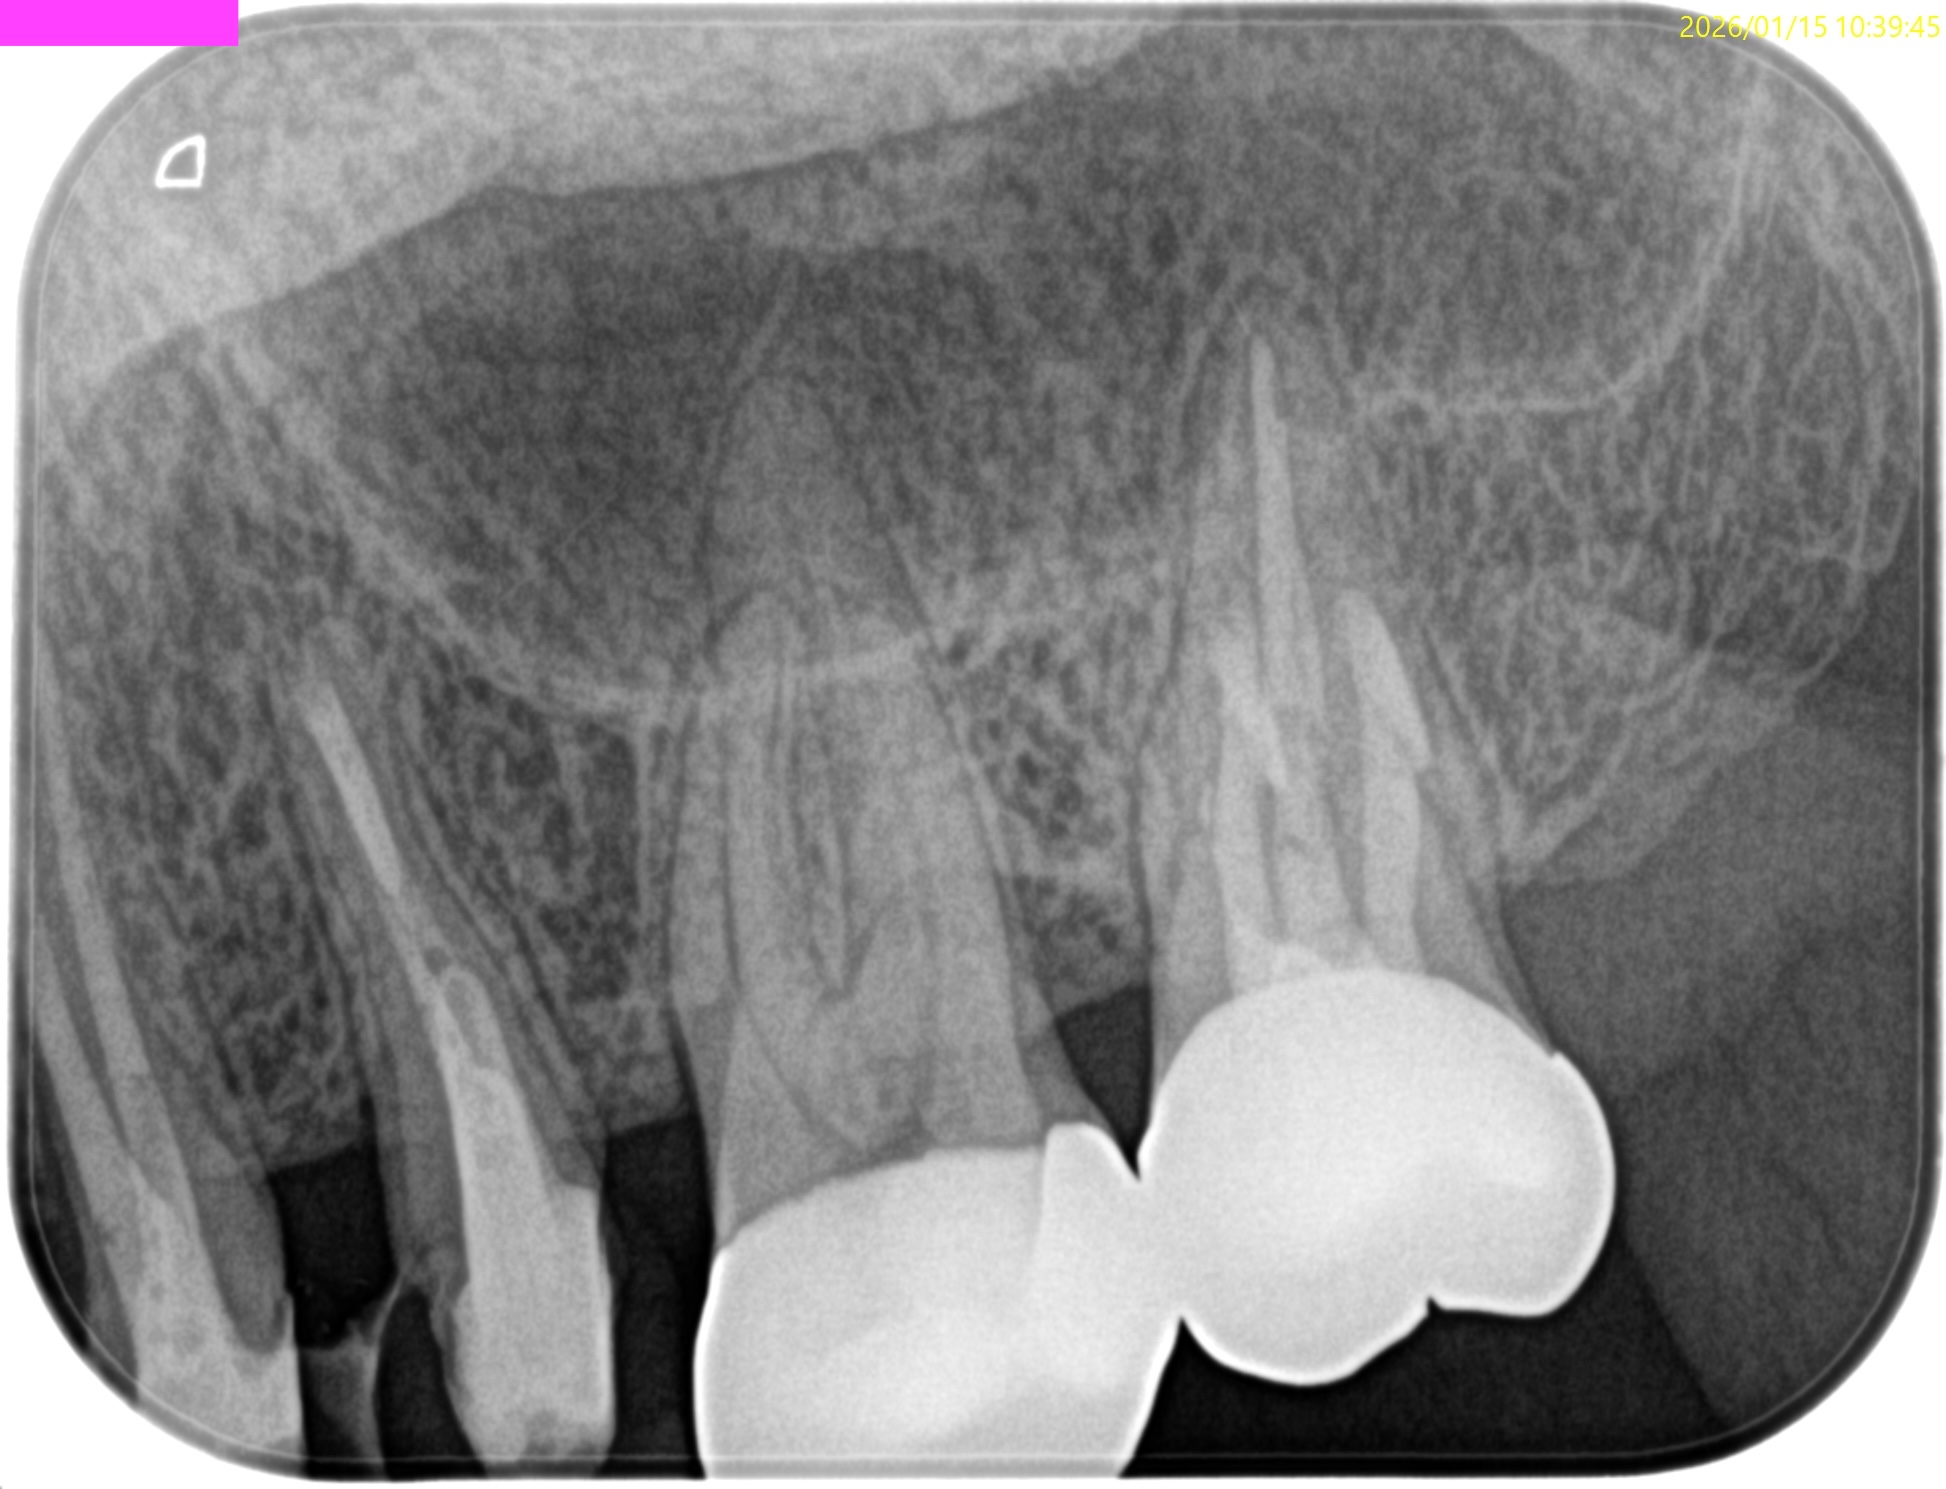

左上7番のMB,DBをApicoectomyしたと言う珍しい?ケースだ。

#15 MB,DB Apicoectomy 1yr recall(2026.1.15)

MB

DB

術前の根尖病変、術直後の歯槽骨の欠損は完治した。